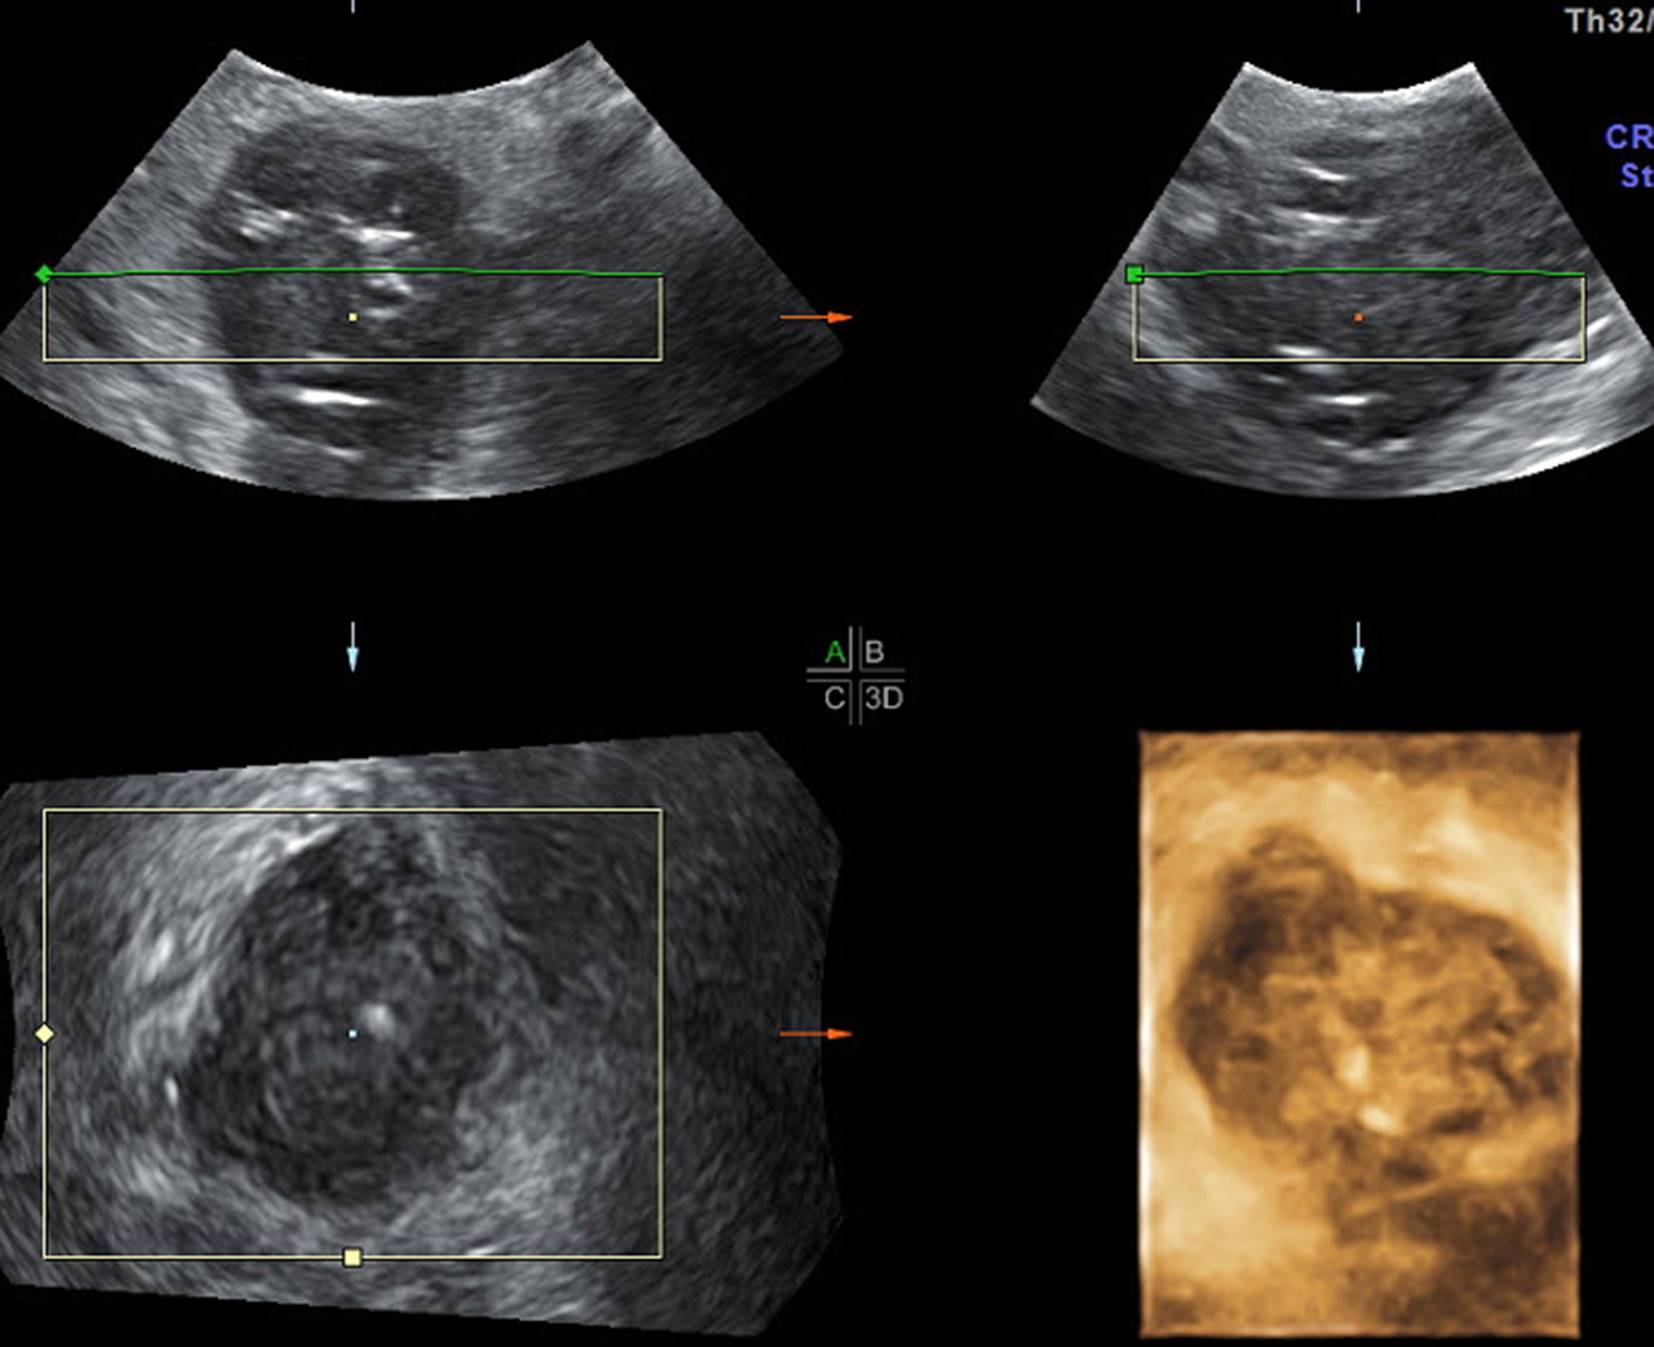

Lassen Sie das Potenzial Ihres Geräts nicht ungenutzt! Uterusfehlbildungen sind im B‑Mode nur mit großem Geschick, Erfahrung und Glück zu erkennen, während dies im 3‑D-Schall auch von abdominal meist rasch und einfach gelingt (Abb. 6). Auch bei der Differenzierung von Adnexzysten ist der 3‑D-Schall hilfreich (Abb. 7). In stimulierten Zyklen, wenn es um die Entscheidung geht, ob und wann die Ovulation medikamentös ausgelöst werden soll, ist zwar grundsätzlich der Vaginalschall zu bevorzugen, da er durch die kürzeren Abstände und meist höhere Auflösung wesentlich präziser ist. Kann aber nur der Abdominalschall zum Einsatz kommen, bringt die 3‑D-Funktion eine wertvolle Befunderweiterung und eine klinische Entscheidungshilfe (Abb. 8a, b).

Abb. 6

Komplett septierter Uterus (U2 nach ESHRE) bzw. partieller Uterus septus (V nach AFS) im Abdominalschall mit 3‑D-Funktion

Abb. 8

a Medikamentös stimuliertes Ovar am 12. Zyklustag mit einem 15 mm-Follikel von abdominal geschallt. b Die Anwendung des 3‑D-Schalls zeigt die im B‑Mode nicht so gut erkennbaren Follikel und hilft bei der Entscheidung, ob in diesem Zyklus eine Ovulation ausgelöst werden soll oder nicht